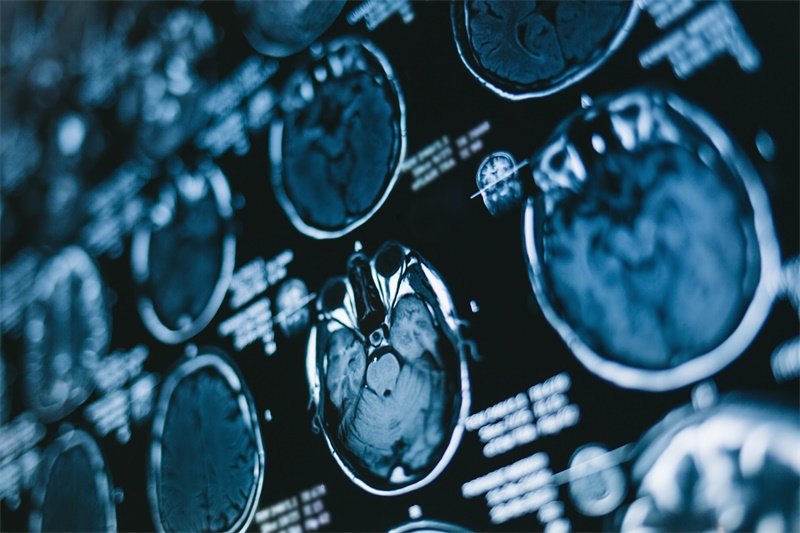

影像学检查

核磁共振成像(MRI)是诊断海马占位性病变的主要方法。MRI能够提供清晰的脑组织图像,帮助医生评估病变的性质、大小和位置。此外,计算机断层扫描(CT)也被应用于某些情况下,能够快速筛查出出血或肿块。